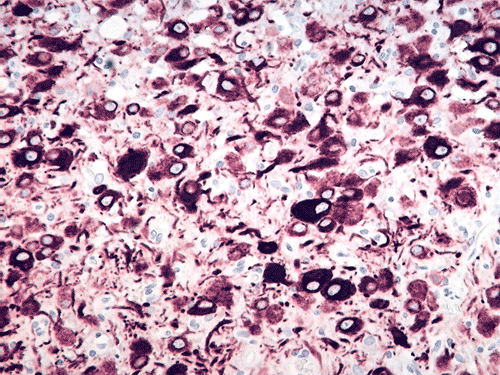

The excised specimen gave the features of cerebellum with greatly expanded cerebellar folia with myelination on the surface of the folia (Panel A, letter S indicates the material used to support the specimen) which can be seen easily on fresh specimen. . The expanded folia are most obvious in fixed specimen (Panel B). On pendicular section of the specimen (Panel C, arrow head points to the pial surface), the normal archicheture of cerebellum is totally effaced. The outer layer is composed of a layer of white matter while the inner half is composed of collections of large, ganglion cells ( in indicates the interface of the two layers which is magnified in Panel D). Multiple calcifications (darks spots in Panel C) are also present.The deeper layers of ganglion cells are composed of large, ganglioinic neurons of similar size and separated by only a small amount of glial tissue (Panel E and F). Multiple calcifications are seen in the more superficial layer of white matter (Panel G). Many calcified blood vessels (Panel H) are also noted in the deeper layers with ganglionic cells. The superficial white matter layer is well myelinated and strongly reactive for neurofilament (Panel I and J, stained by Luxol fast blue- Creysl Violet and immunohistochemistry for neurofilament respectively correspond to the interface indicated by the * in Panel C). The ganglionic cells are stronly reactive for neurofilament protien and synaptophysin (Panel K and L).

Histologically, a layer of myelinated fibers with large diameter myelinated axons is present in the more superficial location of the expanded where the molecular layer is found at the same level in normal cerebellum. The deeper layer where internal granule layer is supposed to be found is replaced by sheets intermediate sized to large dysplastic neurons that resemble Purkinje cells. In high magnification, these areas resemble gangliocytoma. The proportion of the myelinated outer layer and ganglionic inner layer is variable. The normal Purkinje cell layer is not found. Interspersed in between are much smaller neuronal cells with hyperchromatic, small nuclei that resemble hte internal granular layer. This is, therefore, essentially an “inside-out” architecture of the cerebellum with white matter on large ganglionic neuronal layer in the deeper layer. Mitotic figures are exceptional. Ki-67 labeling is 0-2% for the small number of cases that have been studied. The native white matter of the affected folia is atrophic and rarefied. The histologic features are very specific. Immunohistochemistry is not typically required for diagnosis.